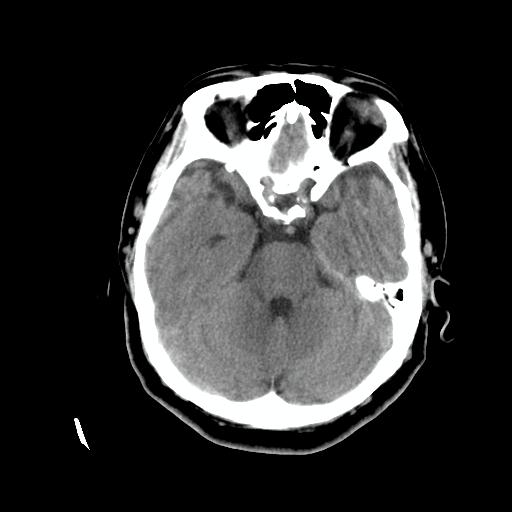

标题: CT24768:双侧脑室内囊性病变,主各位站友会诊。 [打印本页]

标题: CT24768:双侧脑室内囊性病变,主各位站友会诊。

患者女,62岁,临床提供头痛、头晕数月,无恶心及呕吐,近日加重。请各位站友看看,能否定为双侧脑室脉络丛囊肿,如果不能,应考虑什么?谢谢!

脉络丛囊肿属神经上皮性囊肿.好发于双侧脉络膜球,通常于影像检查或活检时偶然发现.患者无症状,病灶较小,双侧对称性,脑室膨胀轻.多数病灶在信号上与室管膜囊肿有所不同.在dwi上呈部分高信号,t2 flair上呈不均匀高信号.增强后呈结节状或环形增强

脉络丛囊肿属神经上皮性囊肿.好发于双侧脉络膜球,通常于影像检查或活检时偶然发现.患者无症状,病灶较小,双侧对称性,脑室膨胀轻.多数病灶在信号上与室管膜囊肿有所不同.在dwi上呈部分高信号,t2 flair上呈不均匀高信号.增强后呈结节状或环形增强!支持!